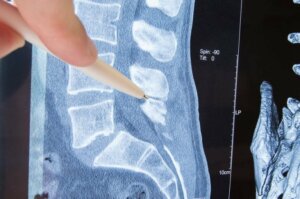

Belkemiği veya omurga, omur tarafından oluşturulan kemikli bir yapıdır. Kemikleri korur ve özgürce hareket etmenizi sağlar. Omurun her bir tarafında delikler bulunur. Bu deliklerden vücudun farklı taraflarına giden sinirler çıkar.

Sinirin omurdan çıkan kısmına “sinir kökü” adı verilir. Radikülopati tam olarak sinir kökünün içinde bulunan sinir sıkışmasıdır. Peki, buna ne sebep olur? Klinik göstergeleri nelerdir? Bu yazıda bu sorulara cevap vereceğiz ve sizi var olan tedavi seçenekleri hakkında bilgilendireceğiz.